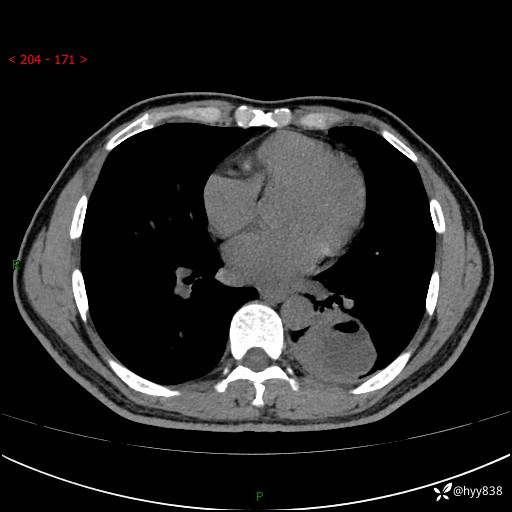

57岁/男,间断痰中带血1月余。纤支镜没有取到东西,穿刺轻松搞定---结果公布~

现病史:患者1月余前无明显诱因出现咯血症状,为痰中带血,量不大,伴轻度咳嗽,2024-3-26于当地市中医医院行胸部CT示:左肺下叶占位性病变。现患者仍有咳嗽不适,无发热乏力,无腹泻、便秘,无咳嗽,无头晕、无双下肢水肿等伴随症状,未行特殊治疗,今日患者再次出现咯血症状。患者为求进一步诊治,遂入我院,门诊以“肺脓肿”收入我科。 患者病程中,精神食欲可,二便正常,体力体重较前变化不明显。

增强